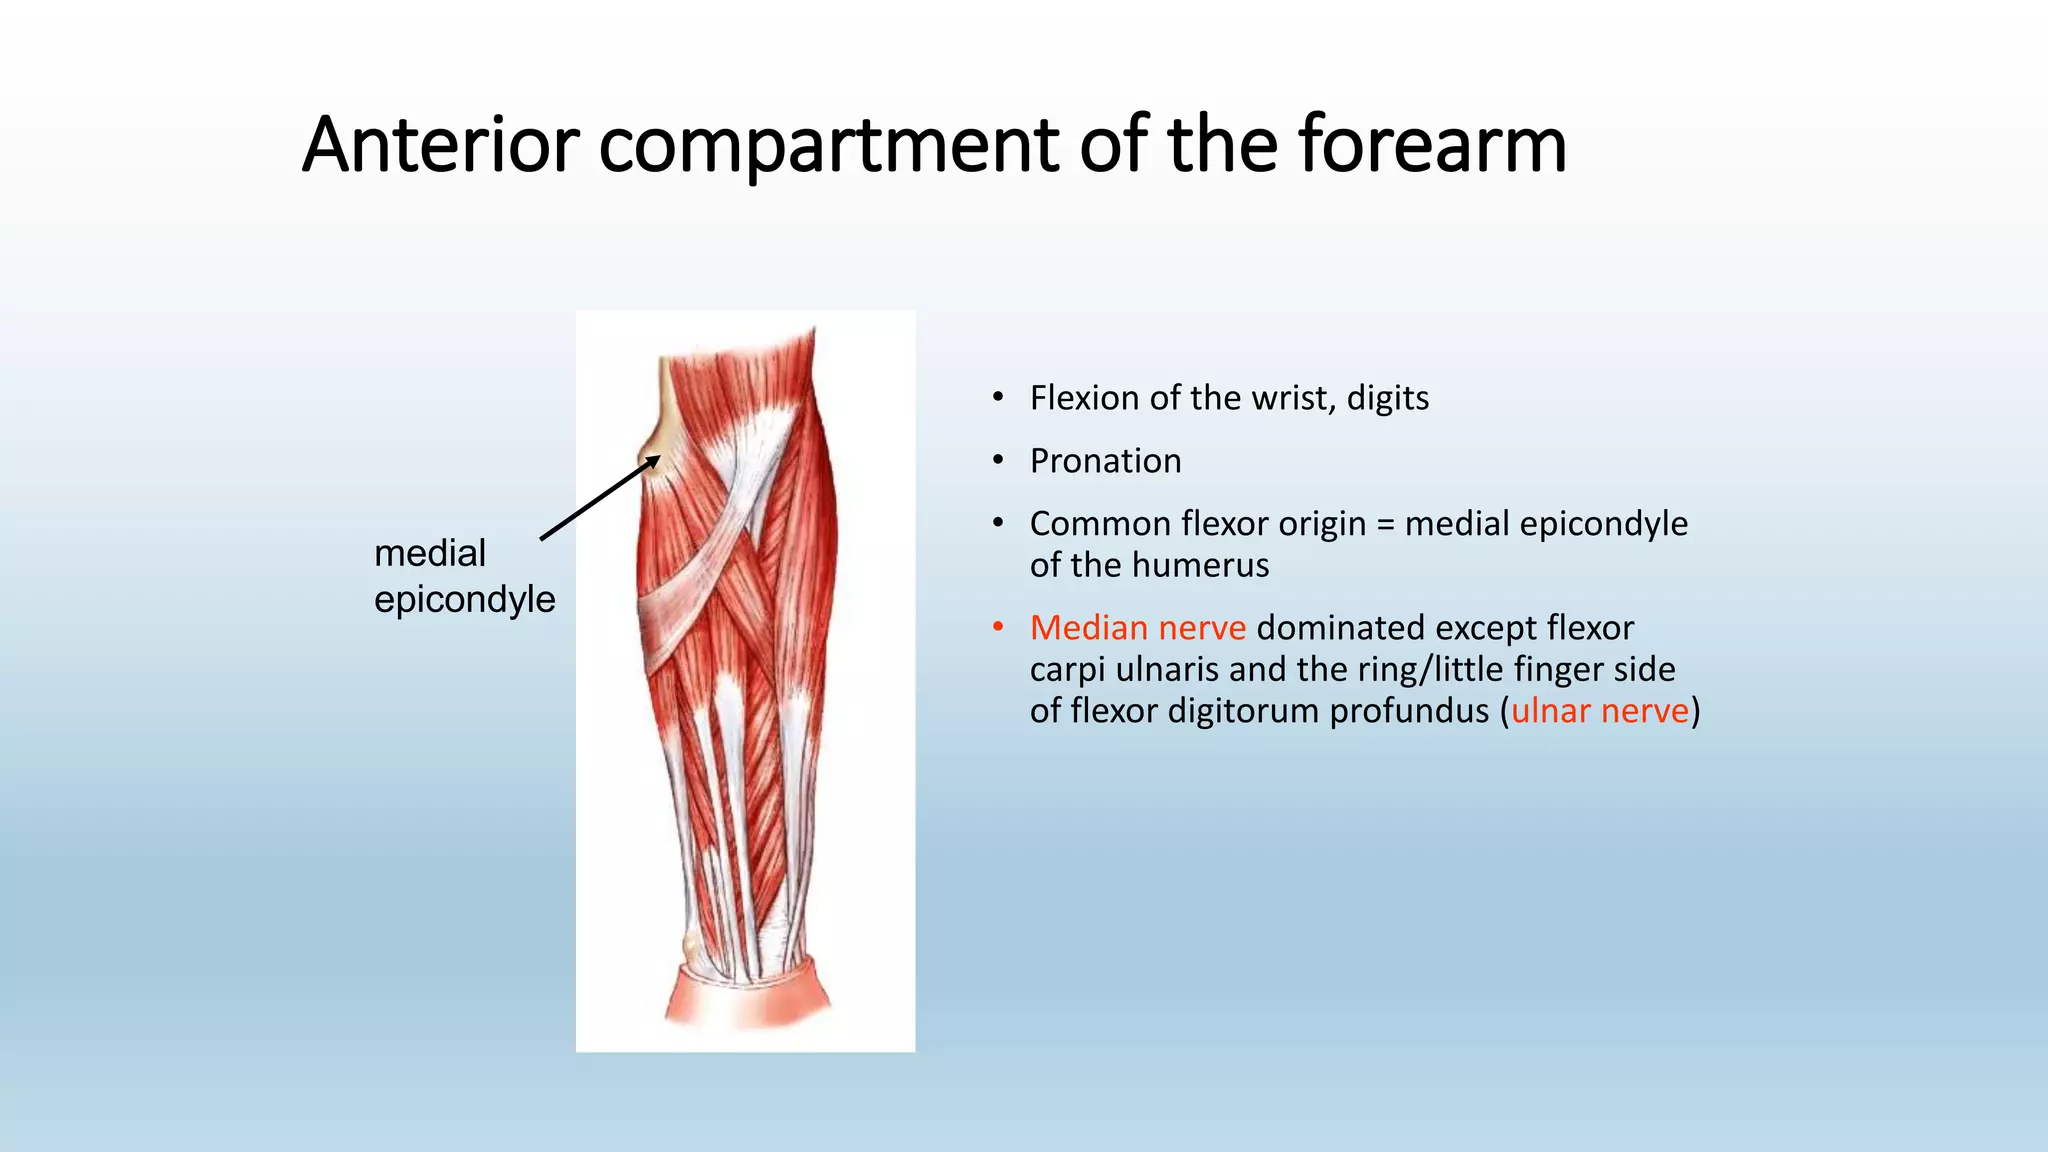

The document summarizes an anatomy revision session on the upper limb. It discusses various muscles of the upper limb including their origins, insertions, innervations and functions. Key muscles covered include the pectoralis major and minor, serratus anterior, deltoid, biceps brachii, brachialis, coracobrachialis, and triceps. It also discusses the rotator cuff muscles and muscles of the forearm including flexor carpi ulnaris and radialis. The session aims to help students identify upper limb muscles and understand their relations to nerves.